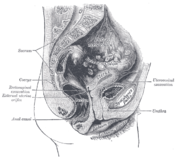

The urethra transports urine from the bladder to the outside of the body. This image shows (a) a human female urethra and (b) a human male urethra. | |

In the human female, the urethra is about 4 cm long,[7] and exits the body between the clitoris and the vagina, extending from the internal to the external urethral orifice. The meatus is located below the clitoris. It is placed behind the symphysis pubis, embedded in the anterior wall of the vagina, and its direction is obliquely downward and forward; it is slightly curved with the concavity directed forward. The proximal two-thirds of the urethra is lined by transitional epithelial cells, while the distal third is lined by stratified squamous epithelial cells.[11]

Between the superior and inferior fascia of the urogenital diaphragm, the female urethra is surrounded by the urethral sphincter.

إحليل الأنثى

في الأناث، يكون طول الإحليل 1-1,5 انش (2,5-4سم) وتكون فتحته في نهاية الفرج بين البظر وفتحة المهبل.